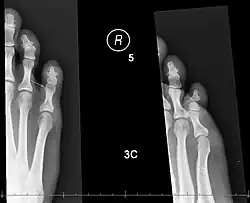

| X-rays of fractures of the proximal (left) and distal (right) phalanges in the little toe. | |